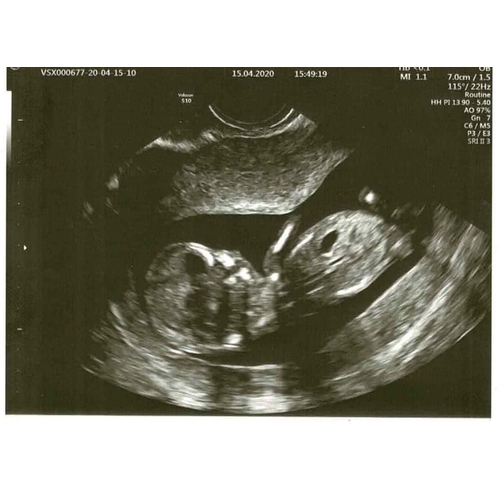

Eigenlijk niets.. het viel me gewoon op dat er bij mij geen neusje te zien is, tov andere echo's. Intussen wat aan andere mensen laten zien en ze denken dat de foetus gedraaid is, en daarom het neusje niet zichtbaar is. En t neusje is niet gelijk aan t neusbotje, dat wist ik niet (ookal is dat superlogisch eigenlijk..).